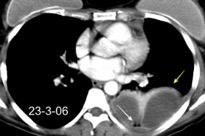

Marzo 2014: Perforación longitudinal distal secundaria a episodio de vómito (síndrome de Boerhaave). Derrame pleural izdo. que evoluciona a empiema.

Wang C-T et al. Tension hydropneumothorax in a Boerhaave syndrome patient: A case report . World J Emerg Med, 2021. Katabathina V et al. Nonvascular, nontraumatic mediastinal emergencies in adults:a comprehensive review of imaging findings. Radiographics. 2011.